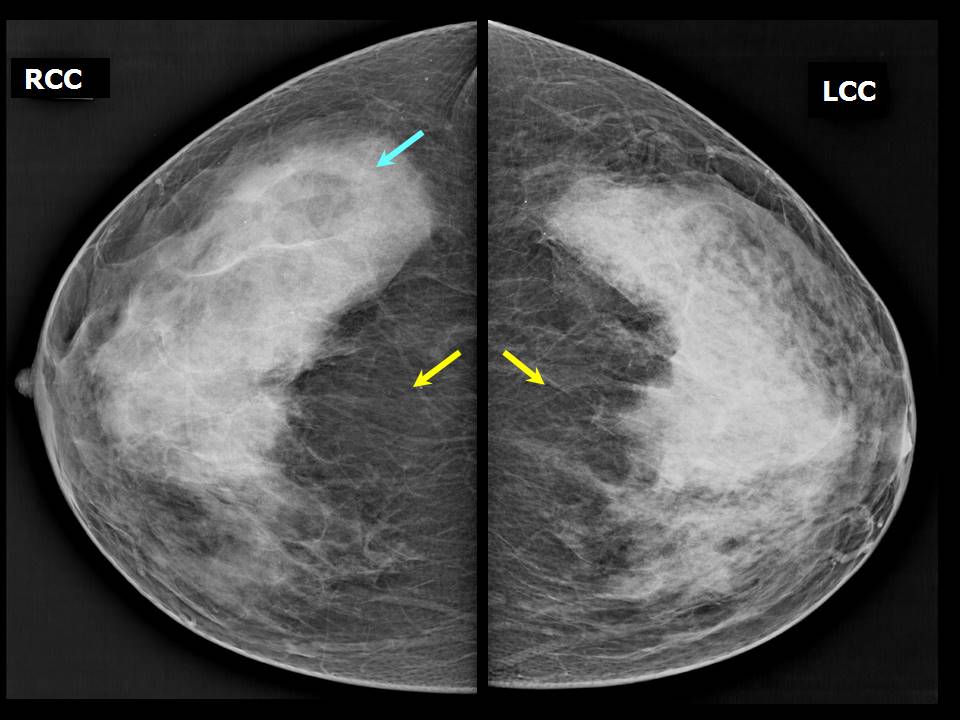

Феномен гипердиагностики в маммографии: примеры и иллюстрации

Раздел: Образы вокруг